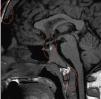

Alteraciones endocrinológicas en un paciente con talasemia mayor

Endocrinological disorders in a patient with thalassemia mayor

Figuras (2)